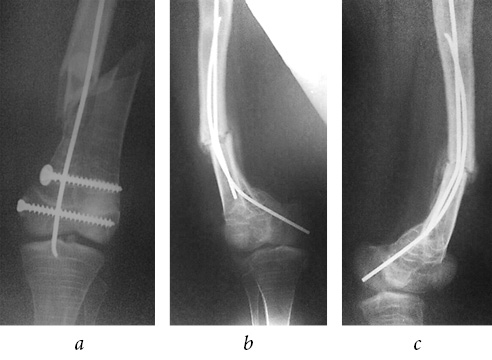

However, initial signs of the formation of a false joint were determined on the radiographs 6 months postoperatively (Fig. 12 a); therefore, an increase in axial load was recommended. The patient walked on crutches with a full load on the left lower extremity and she did not complain of pain or pathological mobility. Radiographs at 1-year follow-up revealed an improvement in the consolidation of the re-implant fracture of left femur. Radiographs at 2-year follow-up showed signs of complete consolidation of the fracture (Fig. 12 b, c).

Fig. 12. Plain radiograph 6 months postoperatively, initial signs of formation of a false joint of the left femoral shaft, complete consolidation of the right femoral fracture (a); radiographs of the left knee joint 2 years postoperatively (b); signs of complete consolidation of the left femoral fractures 2 years later (c)